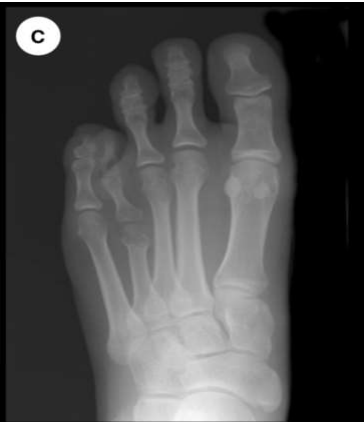

Fig: 1 The radiographs show an anteroposterior view of before and after operation of bone graft.

Figure 2